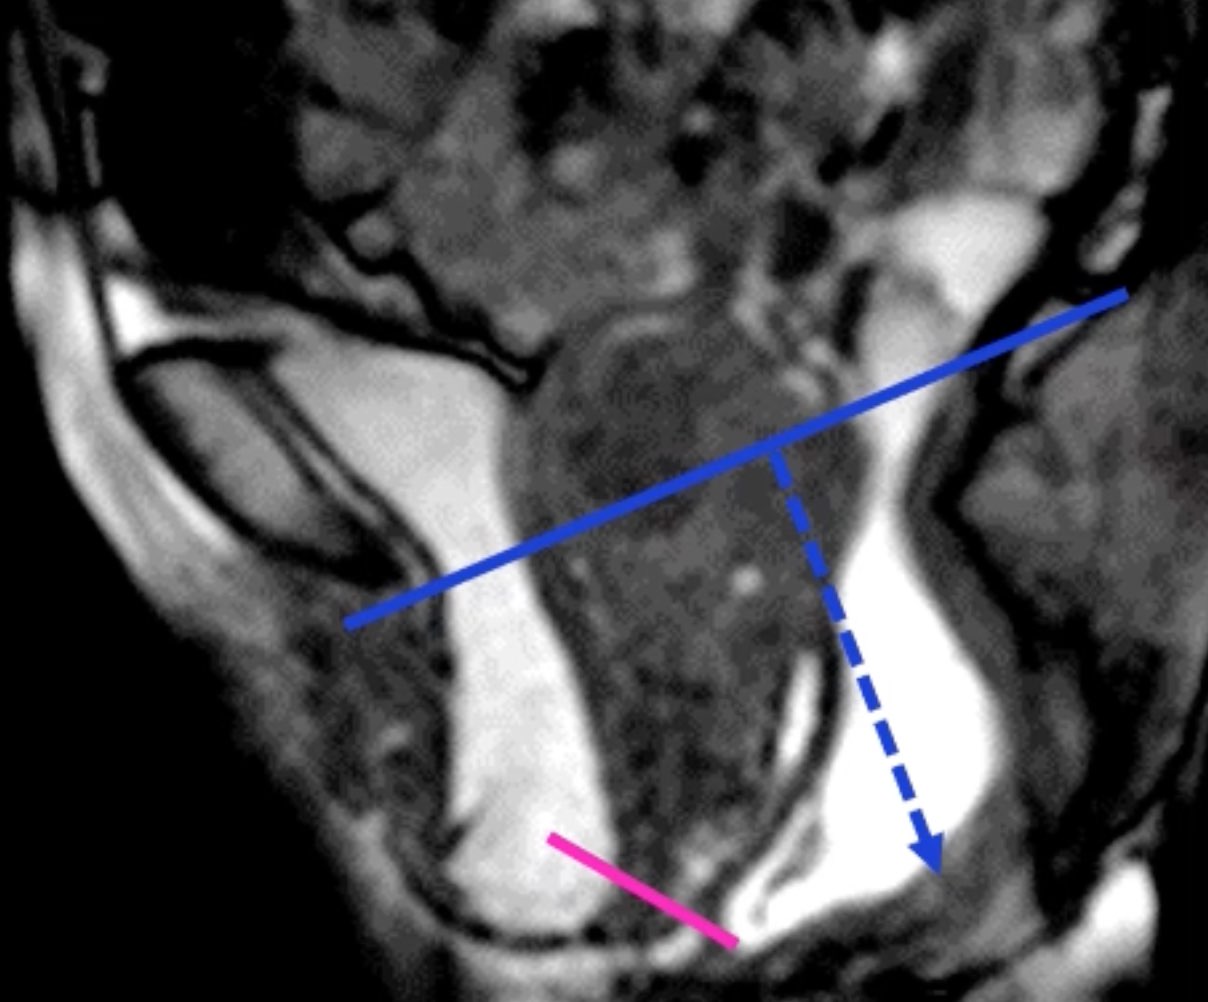

Asynchronisme ano-rectal = anisme

fermeture paradoxale du muscle élévateur en poussée

fermeture paradoxale du muscle élévateur en poussée

Périnée descendant

> 6 cm sous la ligne pubo-coccygienne

> 6 cm sous la ligne pubo-coccygienne